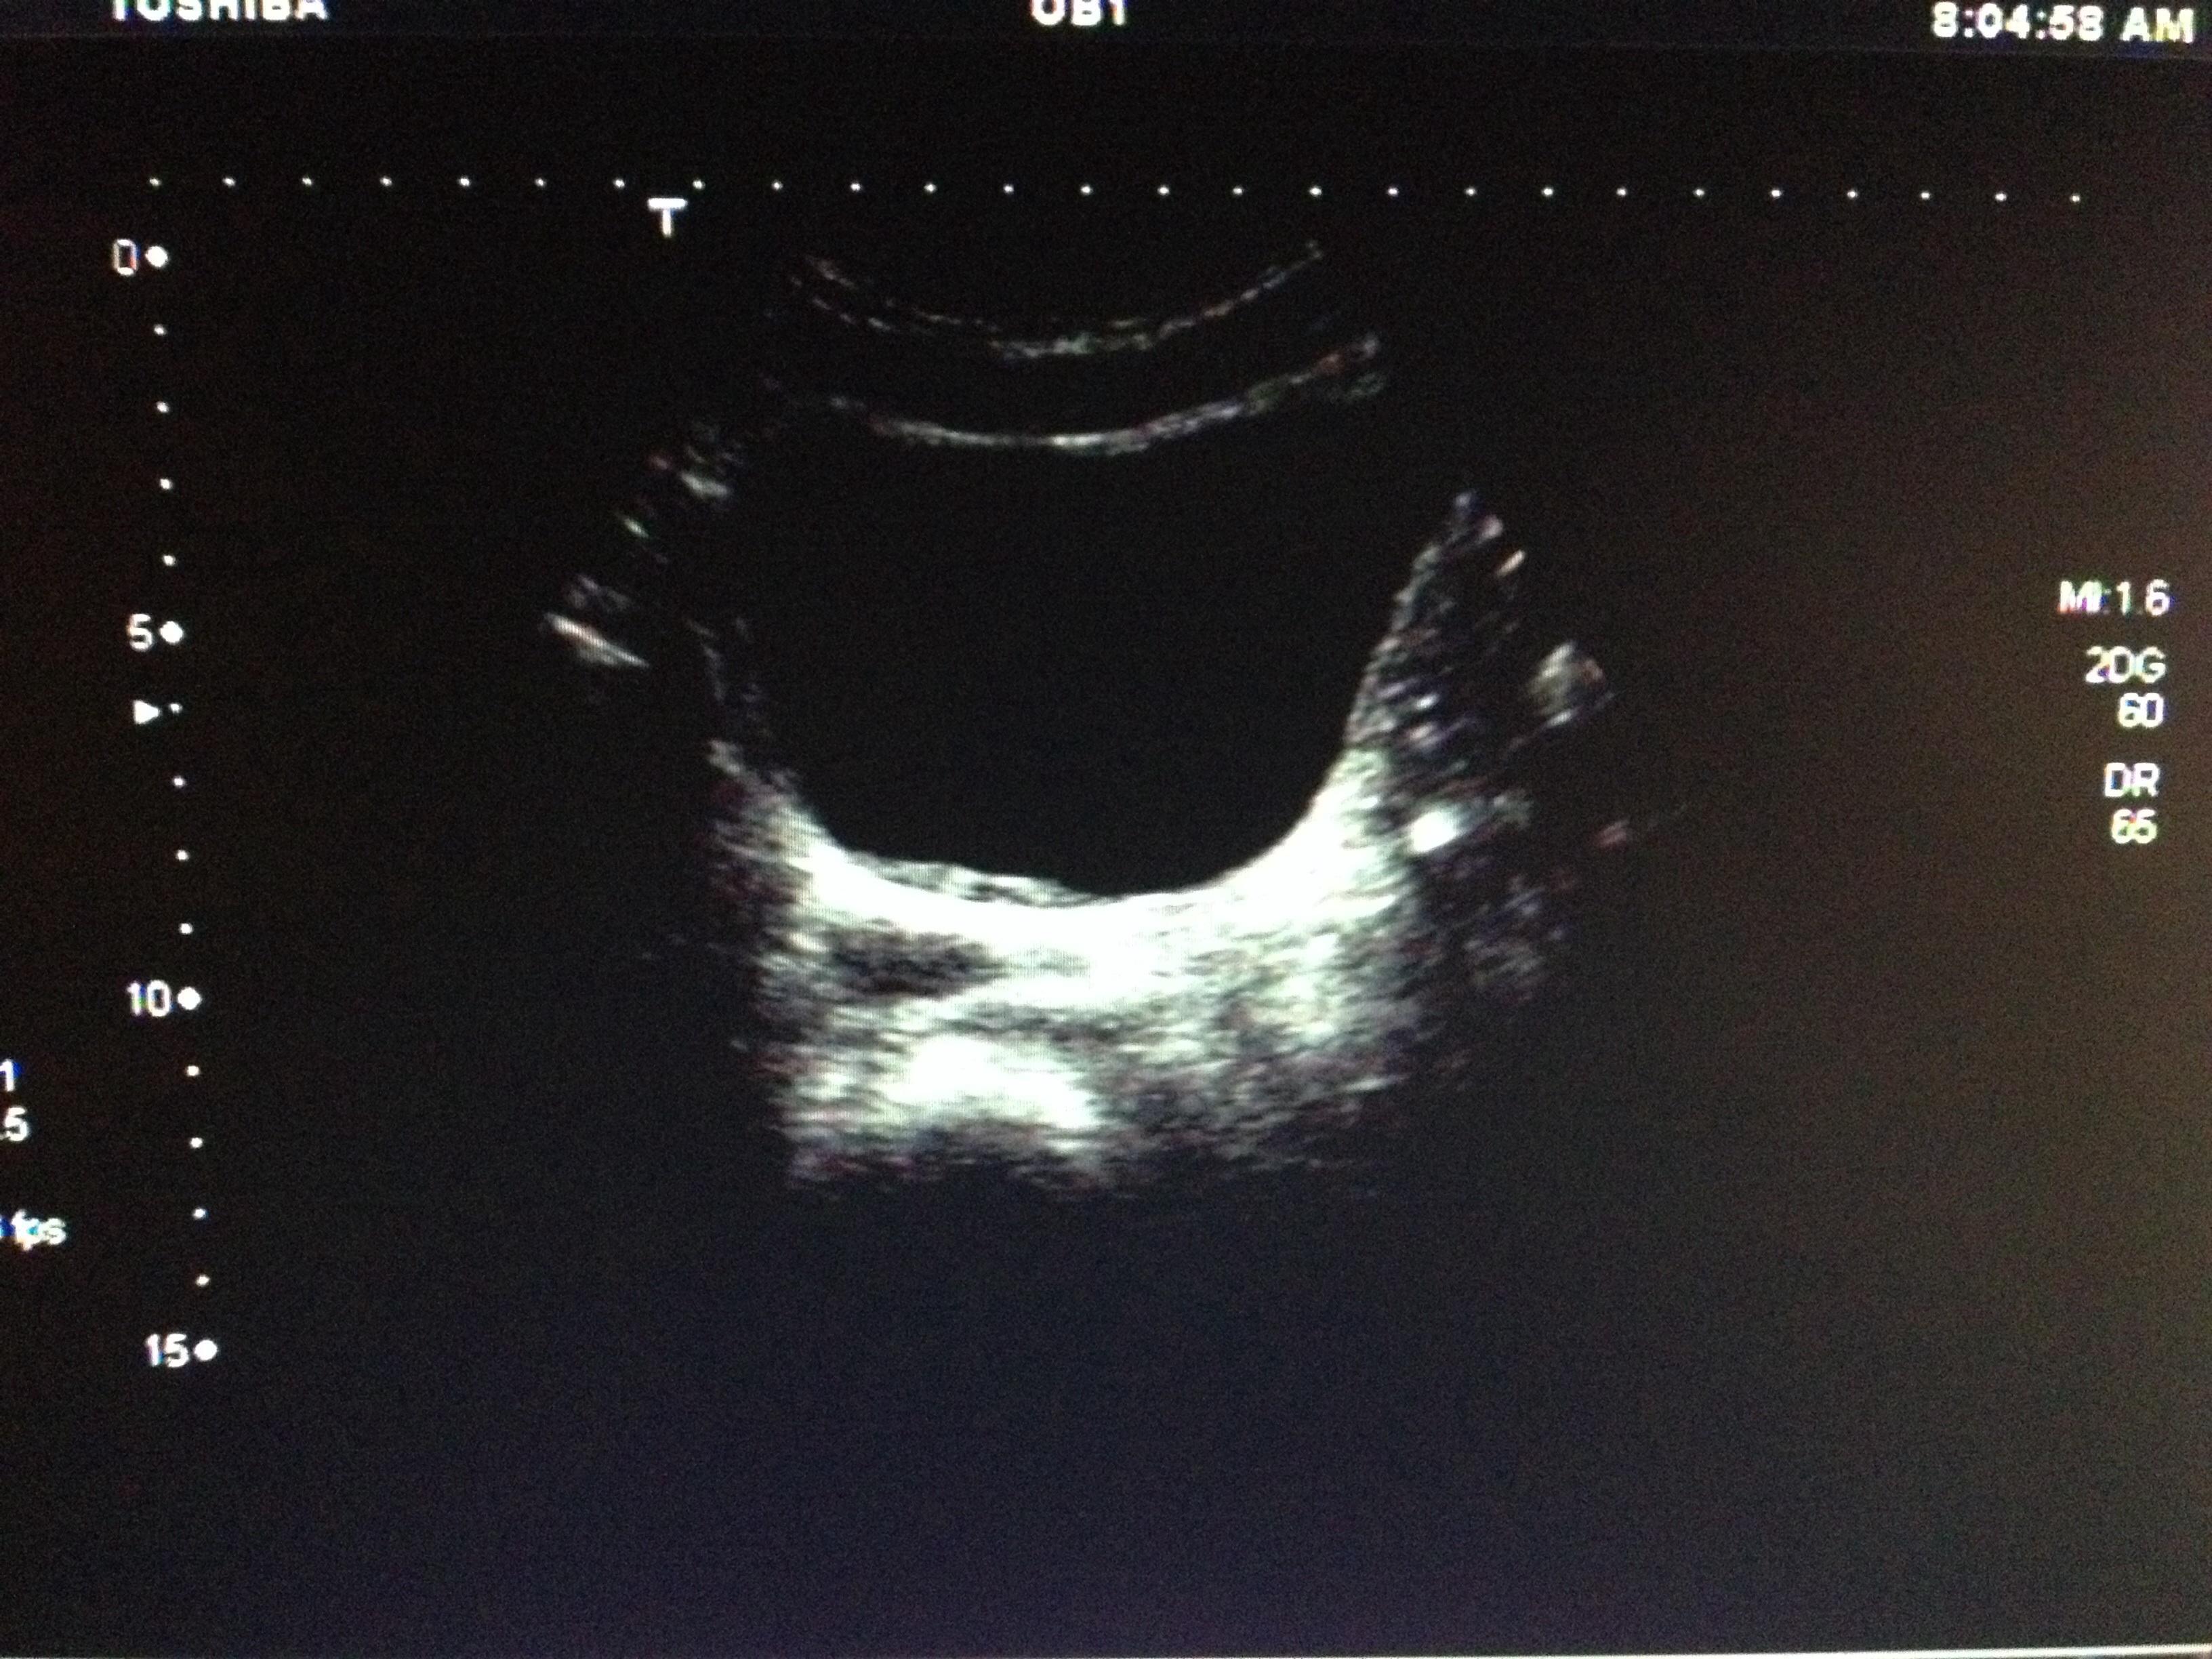

帮忙看看这个图片膀胱后壁内膜增厚吗

图片尺寸3264x2448